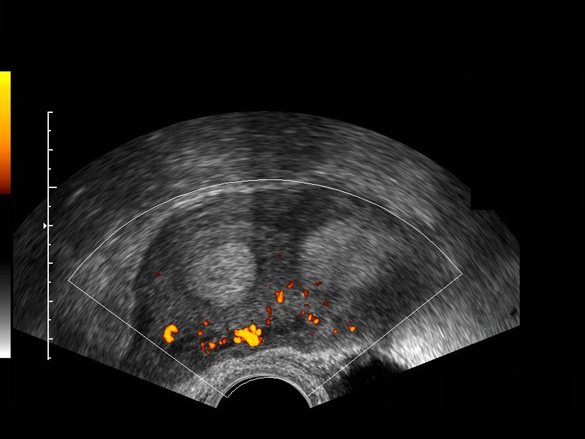

Utérus cloisonné sub-total, vascularisation